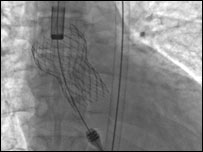

The surgery is done through a small incision in the skin

The new technique involves a short operation to implant the valve using a catheter.